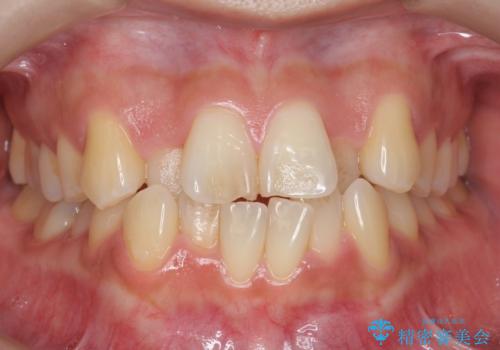

- 前歯のがたつき、受け口を主訴に来院。

上の前歯が二本裏側に入っていました。(反対咬合といいます)

上はワイヤー部分矯正、下はインビザライン(マウスピース)で部分矯正を行いました。

下の前歯を内側に入れる為、一本抜歯しています。

上の前歯のデコボコは激しく、かぶせ物で治療するとなると2本抜歯してブリッジになってしまいます。ダミーの歯の大きさも小さくなるため不自然になり下の歯のがたつきもあるためお勧めできません。

全体矯正で治そうとすると非抜歯ですとだいぶ口元が前に突出するのに加え、下の前歯が入りきらない可能性がありました。上下左右4本抜歯となるため、それを回避するのに下の前歯を1本抜歯して、下の前歯を確実に内側に入れています。